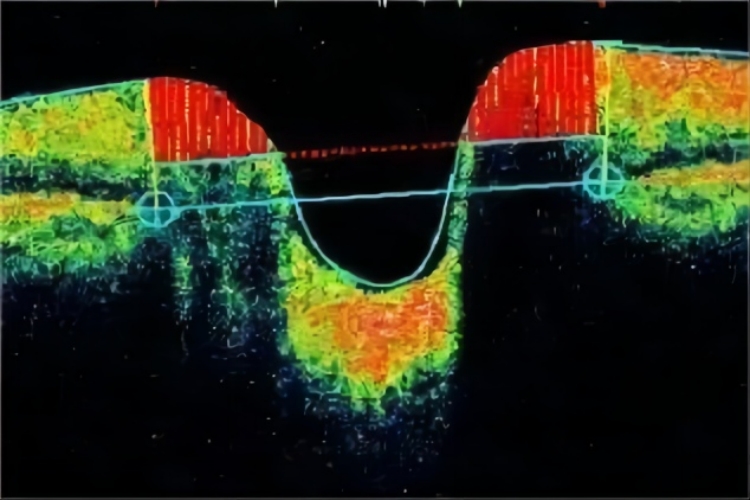

视盘凹陷扩大:以视盘为中心进行视盘多条放射状断层扫描,可清楚地显示视盘轮廓和视盘凹陷。青光眼视盘改变在OCT图像中表现为视盘头凹陷加深、视杯扩大。视盘小坑往往也伴有视杯扩大。